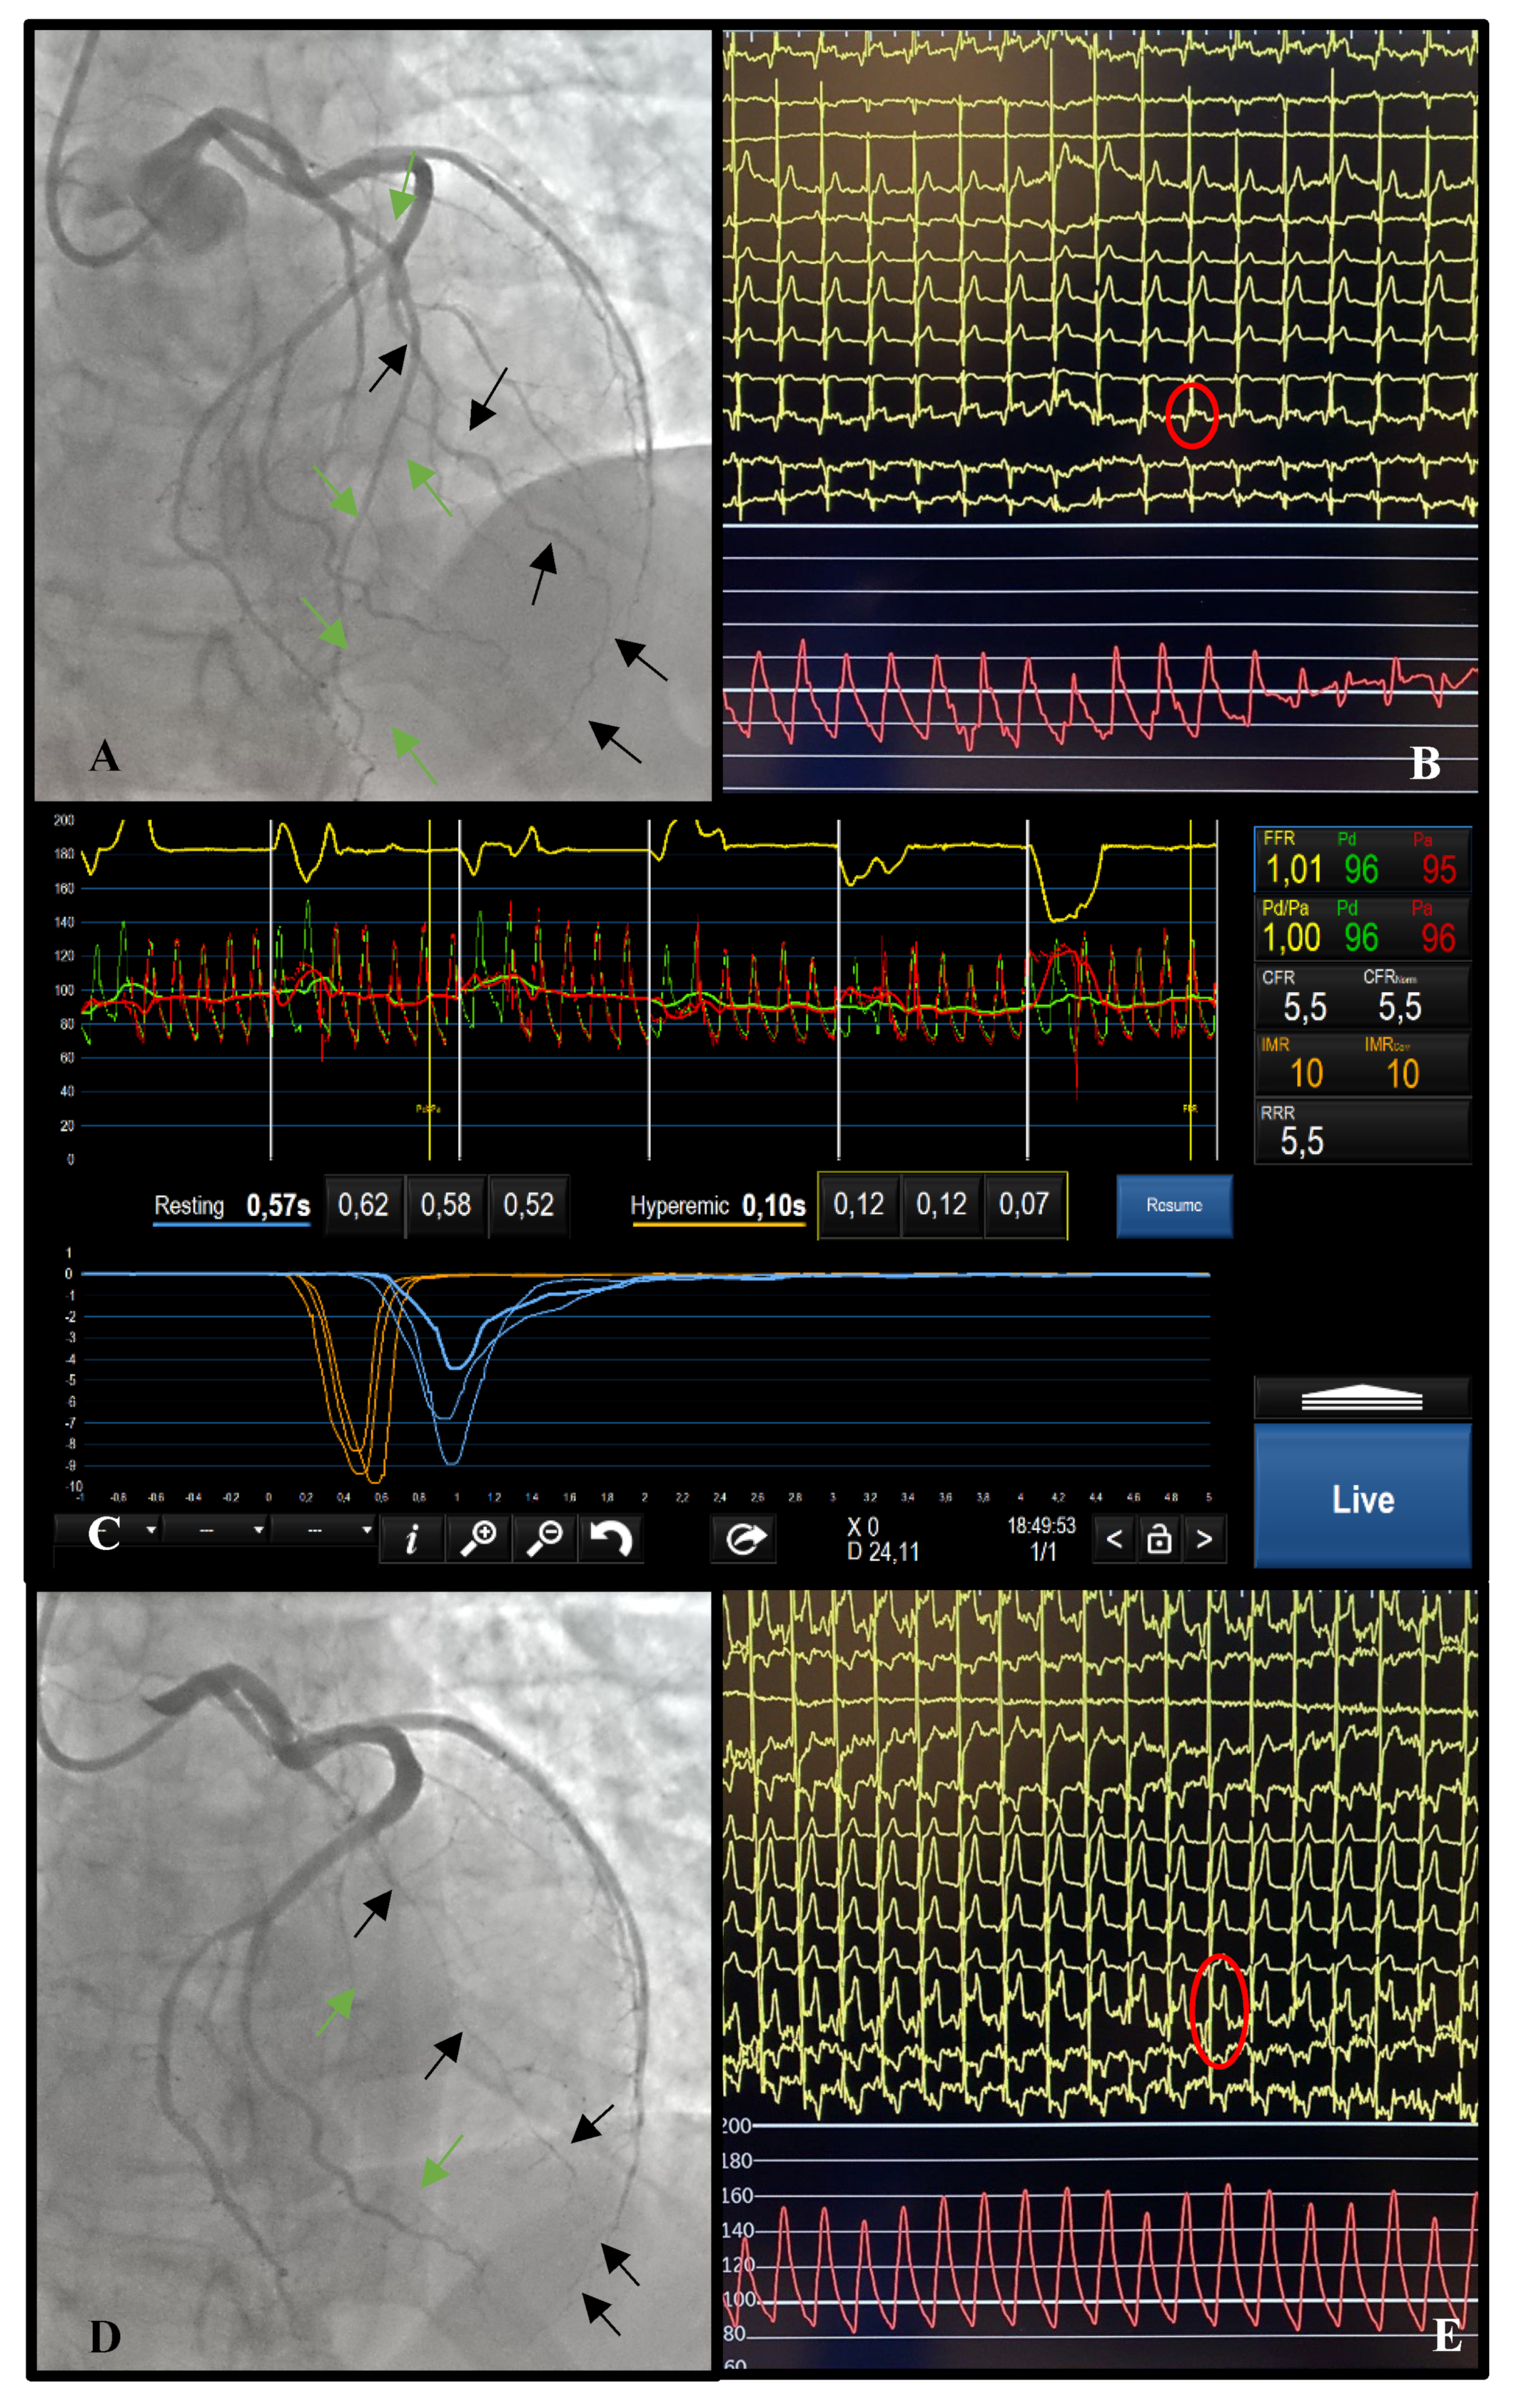

2. Epicardial Disease

2.1. Diagnosis

2.2. Post-PCI Assessment

3. Microvascular Disease